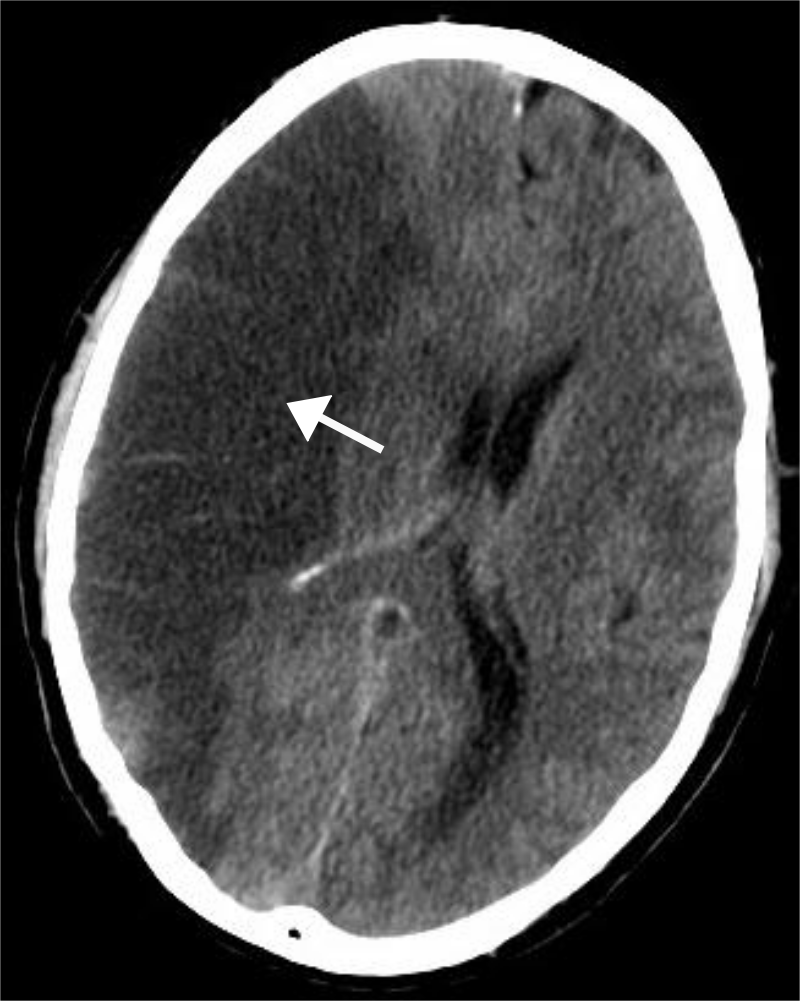

Intracerebral Hemorrhage

An intracerebral hemorrhage is due to brain parenchyma bleeding.

Intracerebral hemorrhage may result from:

- Lenticulostriate vessel rupture

- Aneurysm rupture

The most typical location of the brain involved by intracerebral hemorrhage is the basal ganglia.

Intracerebral hemorrhage hemorrhages may be caused by hypertension.